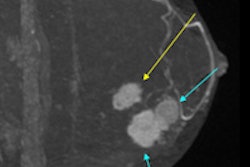

Meanwhile, researchers from a top South Korean facility have studied patients who underwent mammography, digital breast tomosynthesis plus mammography, and MRI plus mammography. They have just published their findings in European Radiology, and their comparison of these modalities is very revealing. Visit our Women's Imaging Community, or click here.